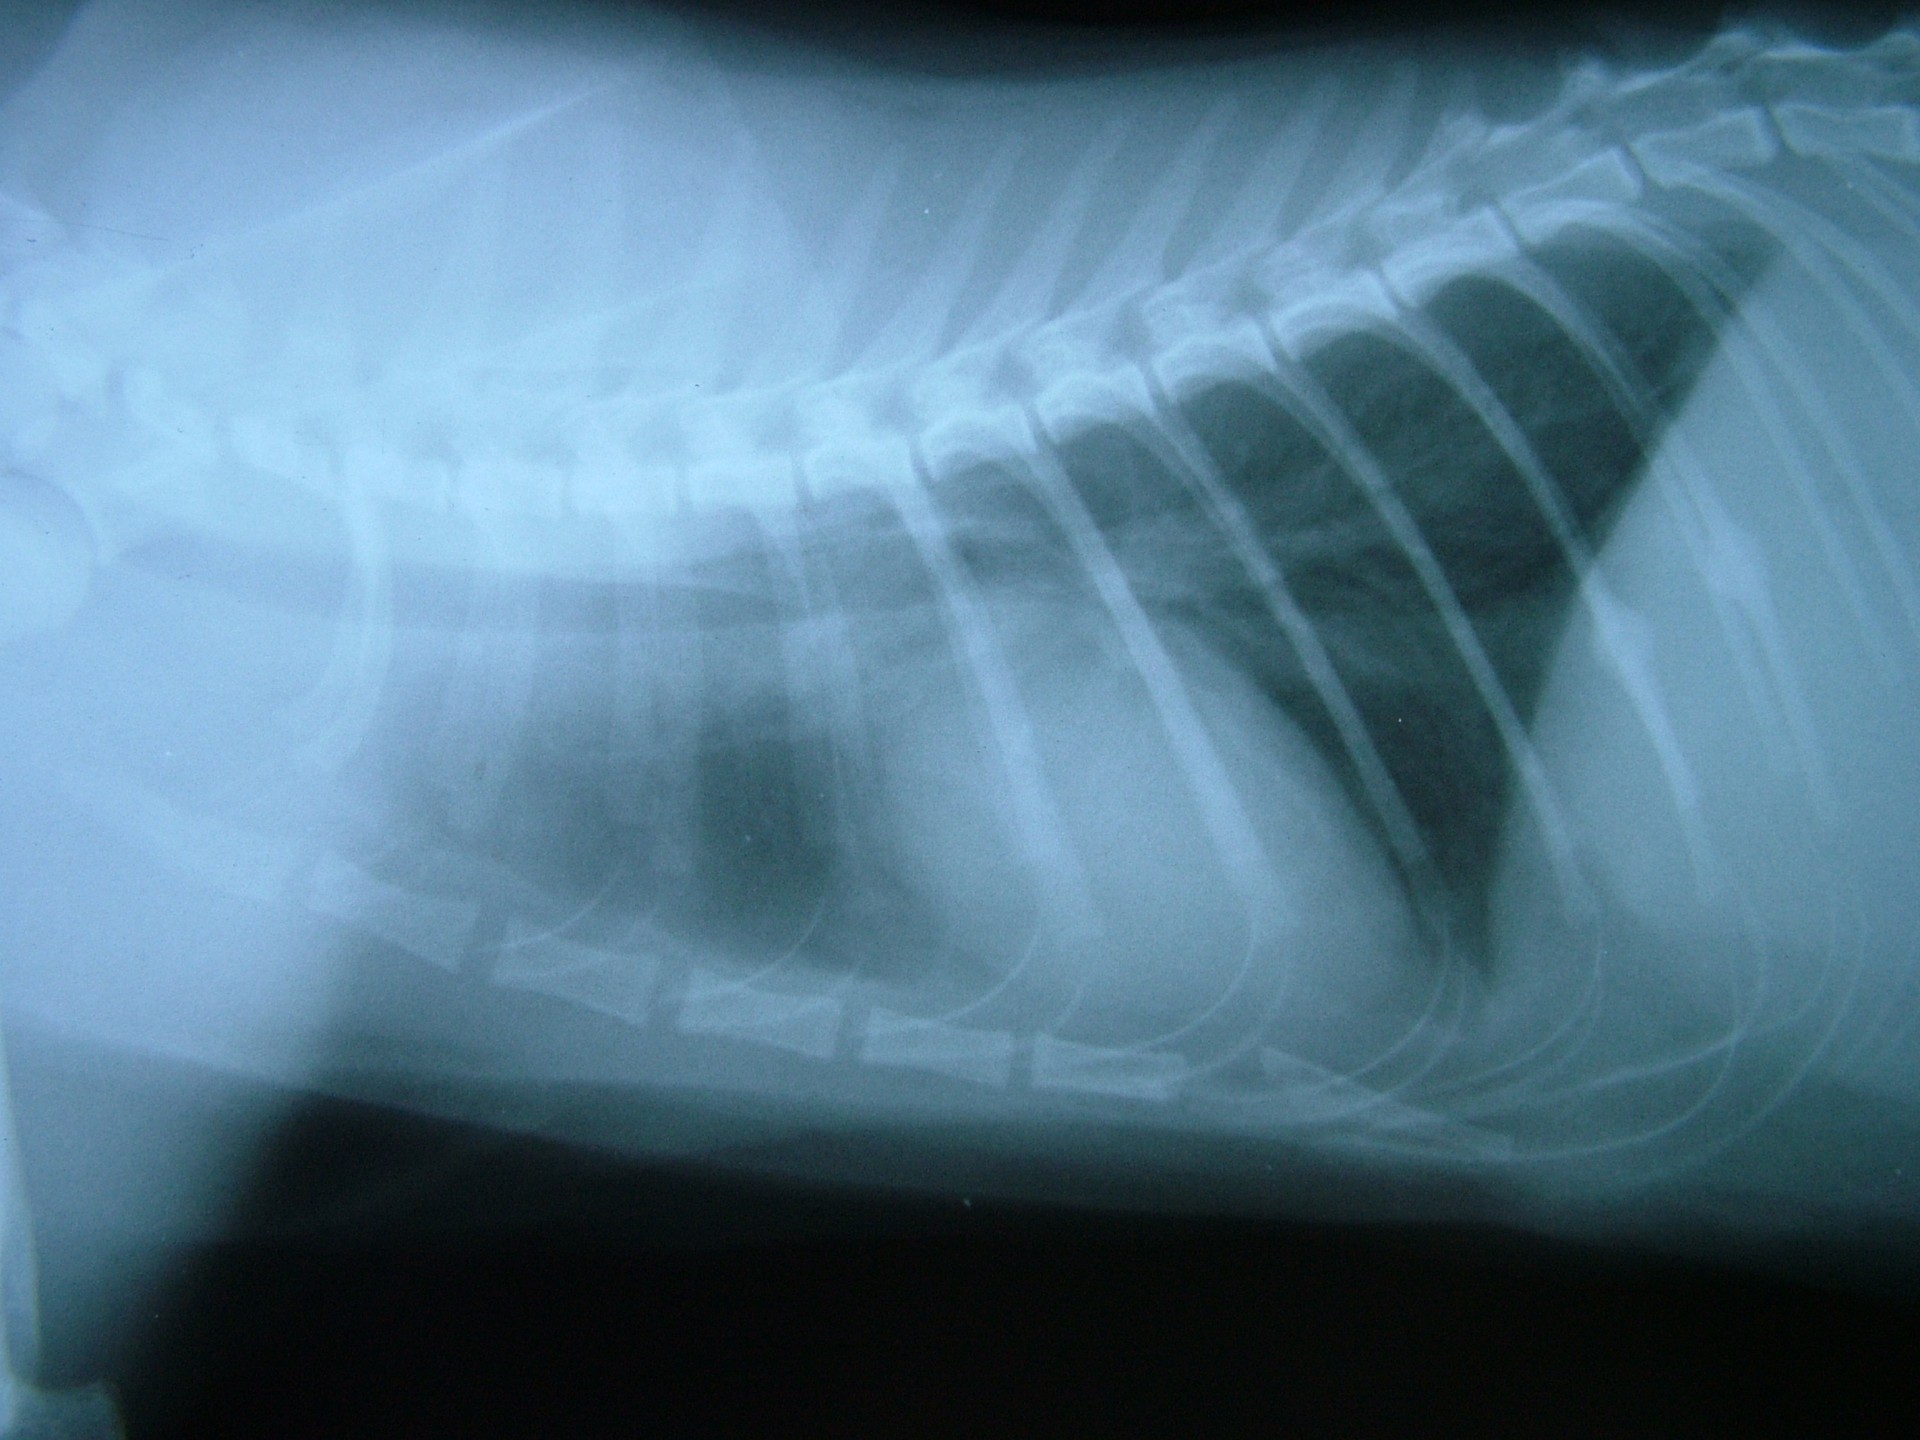

A rekeszizom veleszületett vagy szerzett sérülése, folytonosság hiánya következtében a hasüregi szervek a mellkasba nyomulnak, és összenyomják a tüdőt. Ennek következtében a tüdő nem képes a mellkas mozgását követni és elsősorban a belégzés folyamata korlátozottá válik.

Mindhárom rekeszsérv forma meglehetősen ritkán fordul elő. A diagnózis felállítása a kórelőzmény, a klinikai tünetek a mellkas röntgenvizsgálata, a hasüreg ultrahangos vizsgálata alapján lehetséges.A rekeszsérv műtéti ellátása során a legnagyobb kihívást az jelenti, hogy a hasüreg megnyitását követően a sérvkapun keresztül levegő kerül a mellüregbe, ezáltal az állat spontán légzése leáll, így a műtét teljes ideje alatt asszisztált lélegeztetésre van szüksége.A műtét során a mellkasba előesett szerveket reponáljuk, a rekesz folytonosság hiányát megszüntetjük és a mellkasban lévő szabad levegőt eltávolítjuk, ezzel biztosítva az állat spontán légzését. A műtétet követő napokban legfontosabb feladat a vérkeringés és a légzés folyamatos, kórházi körülmények közötti kontrolálása.Az idejében felismert és megfelelően ellátott veleszületett rekeszsérv jó eséllyel gyógyítható, a traumás eredetű sérv ellátásának eredményességét általában az egyéb szervek sérülése határozza meg.